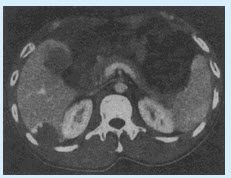

(单选题)双肾CT增强扫描图像如下,可诊断为()

A:肾癌

B:肾盂癌

C:肾囊肿

D:肾错构瘤

E:肾母细胞瘤